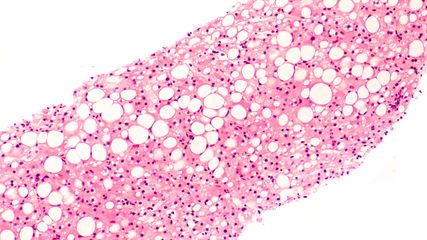

In der Indikation metabolisch bedingte Lebersteatose bzw. Steatohepatitis scheiterten über viele Jahre zahlreiche Therapieversuche. Seit Kurzem stehen erstmals wirksame und zugelassene Therapien zur Verfügung. Als effektiv erwiesen haben sich Substanzen aus der Gruppe der GLP-1-Rezeptor-Agonisten sowie Resmetirom, ein selektiver Agonist am Schilddrüsenhormonrezeptor β.

Die Arbeitsdiagnose einer MASLD (mit metabolischer Dysfunktion assoziierte steatotische Lebererkrankung – bis vor Kurzem als NAFLD bezeichnet) ist einfach: Wird mittels Bildgebung, in der Regel Ultraschall oder Biopsie, eine Steatose der Leber festgestellt und liegen kardiometabolische Risikofaktoren, jedoch kein hoher Alkoholkonsum vor, so kann von einer MASLD ausgegangen werden. Kommen Inflammation und möglicherweise Fibrose hinzu, so spricht man von MASH (mit metabolischer Dysfunktion assoziierte Steatohepatitis). Bei 80% der Betroffenen bleibt es bei einer Steatose mit allenfalls minimalem Progressionsrisiko, erläuterte Univ.-Prof. Dr. Herbert Tilg, Leiter der Innsbrucker Universitätsklinik für Innere Medizin I. In 20% der Fälle liegt jedoch eine MASH vor, die mit einem beträchtlichen Risiko für Progression zu Zirrhose und Dekompensation sowie mit einer erhöhten Inzidenz von Leberkarzinomen assoziiert ist. In dieser Patientengruppe ist die Mortalität signifikant erhöht, wobei kardiovaskuläre Todesursachen die größte Rolle spielen. Daher besteht erheblicher Bedarf an wirksamen Therapien, so Tilg, der ergänzte, dass man bis heute nicht vollständig verstehe, warum es bei der Mehrheit der Betroffenen bei MASLD bleibt, während ein Teil eine MASH entwickelt. Dabei dürften extrahepatische Signale, unter anderem aus dem Fettgewebe, aber auch bakterielle Stoffwechselprodukte aus dem Darmmikrobiom eine wichtige Rolle spielen.1